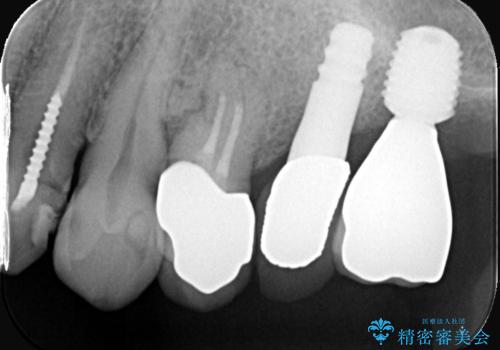

歯根破折により抜歯となり、インプラント治療(一回法)にて補綴修復を行いました。

抜歯から3か月程骨ができてくるのを待ってからインプラントを埋入しています。

埋入時には上顎洞粘膜を数ミリ挙上しています。